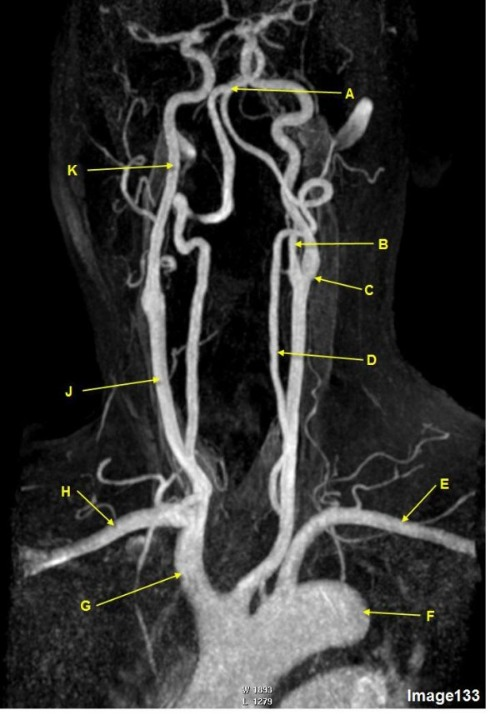

Image 16 is an example of what type of MR image?

A. MR Spectroscopy

B. MRA Circle of Willis

C. MRV intracranial circulation

D. MRA extracranial circulation

E. MRA intracranial circulation

Letter A in Image 16 is pointing to:

A. Internal carotid artery

B. External carotid artery

C. Vertebral artery

D. Common carotid artery

E. Common carotid bifurcation

Letter B in Image 16 is pointing to:

Letter C in Image 16 is pointing to:

Letter E in Image 16 is pointing to:

Letter C in Image 133 is pointing to:

A. Middle cerebral artery

B. Common carotid bifurcation

C. VertebroBasilar junction

D. Internal carotid artery

E. External carotid artery

F. Abdominal aorta

Letter F in Image 133 is pointing to:

C. Brachiocephalic artery

D. Thoracic aorta

E. Subclavian artery

Letter K in Image 133 is pointing to:

A. Vertebral artery

Letter E in Image 133 is pointing to:

A. Right subclavian artery

B. Left subclavian artery

D. Innominate artery

E. Aortic arch

Letter D in Image 133 is pointing to:

Letter E in Image 16 is responsible for blood supply to the:

A. Anterior brain

B. Posterior brain

C. Face

D. Upper extremities

Letter B in Image 16 is responsible for blood supply to the:

Letter A in Image 16 is responsible for blood supply to the: